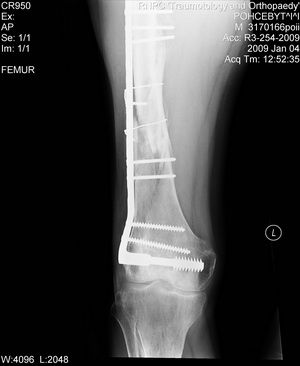

На снимке есть только дистальный отдел бедра, похоже, еще (или уже?) несросшийся на

фоне DCS. Что за перелом проксимального бедра, пока информации нет. Шлите снимки. И узнать бы, что доступно на месте для этого пациента.

Теперь ситуация более ясная. Оптимальным тут, очевидно, было бы малоинвазивное удаление пластины и закрытый интрамедуллярный остеосинтез длинной гаммой или другим проксимальным гвоздем. Это не только обеспечило бы надежную фиксацию всех проблемных отделов бедра, но и позволило бы немедленную полную нагрузку.

Другие варианты менее привлекательны, хотя в итоге могли бы привести к успеху. Но ценой большей травматичности, длительности лечения, неудобств, трудоемкости и с бОльшими рисками неприятностей. Вариантов очень много - скелетное вытяжение, тазобедренная повязка, остеосинтез DHS или другой пластиной с угловой стабильностью, остеосинтез таким или другим аппаратом...